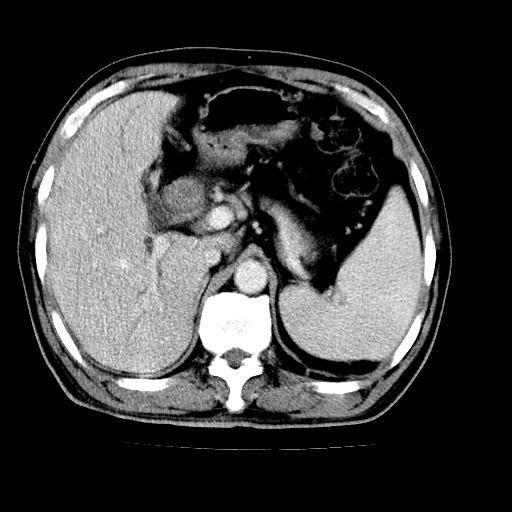

肝左叶不规则软组织肿块影,边缘不规整邻近肝实质受累分界不清;肝内胆管(左叶)明显扩张成“软藤状”,诊断:肝左叶胆管细胞癌。

肝左叶占位性病变,并胆管扩张,符合胆管细胞癌ct表现,门脉左支受累,左肾囊肿。窗宽太窄了,其他的看不清

左叶胆管细胞癌累及胆总管,门脉左支受侵,慢性胆囊炎胆结石,左肾小囊肿

支持肝左叶肝内胆管细胞癌伴胆总管及门脉左支受侵。

肝左叶不规则软组织肿块影,边缘不规整邻近肝实质受累分界不清;肝内胆管(左叶)明显扩张成“软藤状”,诊断:肝左叶胆管细胞癌。胆囊钙乳症。